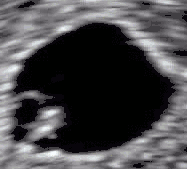

Imagem colorida artificialmente, mostrando saco gestacional, saco vitelino e embrião (medindo 3 mm entre os sinais +)

Embrião com 5 semanas e 1 dia de idade gestacional (no canto superior esquerdo) com batimento cardíaco discernível